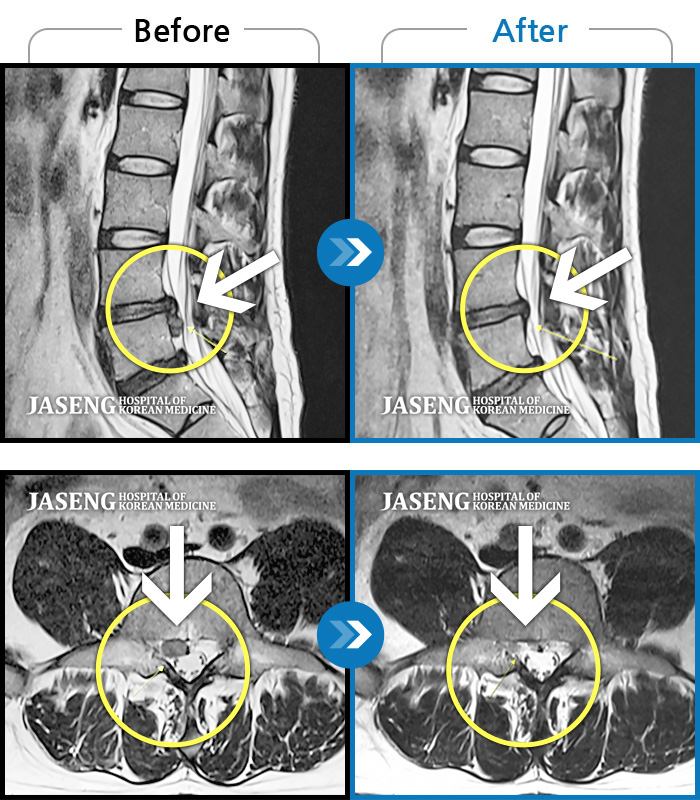

MRI 치료사례

하부 요추, 우측 다리까지 통증. 앉았다가 일어날때, 허리 펼때 통증